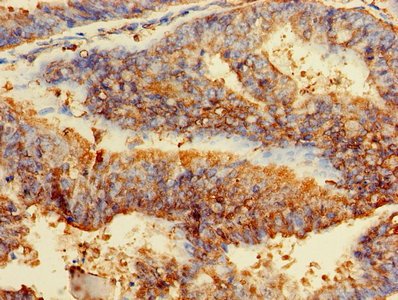

ApplicationELISA, WB, IHC, IF, IP; Recommended dilution: WB:1:500-1:5000, IHC:1:20-1:200, IF:1:50-1:200, IP:1:200-1:2000